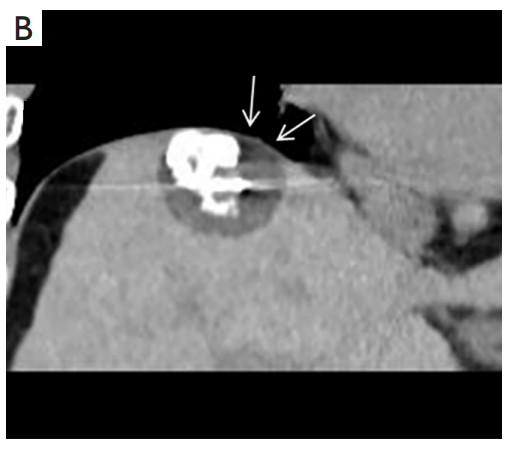

背景:肝癌是中國最常見的惡性腫瘤之一,發(fā)病率和死亡率都很高。雖然手術(shù)切除是最好的治療方法,但大多數(shù)患者處于晚期或直到住院才有手術(shù)指征。對(duì)于單個(gè)腫瘤直徑小于5厘米的患者,微創(chuàng)治療與手術(shù)切除效果相當(dāng);多個(gè)病灶小于3個(gè),單個(gè)病灶最大直徑小于3cm;不侵犯血管、膽管、鄰近器官和遠(yuǎn)處轉(zhuǎn)移。雖然一些傳統(tǒng)消融技術(shù)方式可以使部分患者受益,但不適用于特殊部位肝癌(定義為毗鄰大血管、肝外臟器和重要結(jié)構(gòu)的腫瘤)的治療。冷凍消融作為一種相對(duì)較新的治療方式,具有明顯的冰球效果、療效好、激活抗腫瘤免疫、并發(fā)癥發(fā)生率低等優(yōu)點(diǎn),尤其適用于特殊部位肝癌患者的治療。我們的研究目的是探討CA治療特殊部位肝癌的安全性、可行性和有效性。

① 在我們的研究中,技術(shù)成功率為100%。動(dòng)態(tài)增強(qiáng)MR檢查隨訪1個(gè)月,66例患者首次技術(shù)有效率為65例(98.5%),MR影像學(xué)未發(fā)現(xiàn)外周臟器損傷。中位隨訪時(shí)間14個(gè)月(范圍2-28個(gè)月)。高危部位肝癌局部腫瘤進(jìn)展率曲線:6、9、15和24個(gè)月的累積局部腫瘤進(jìn)展率分別為10.2%、16.5%、20.9%和30.5%。